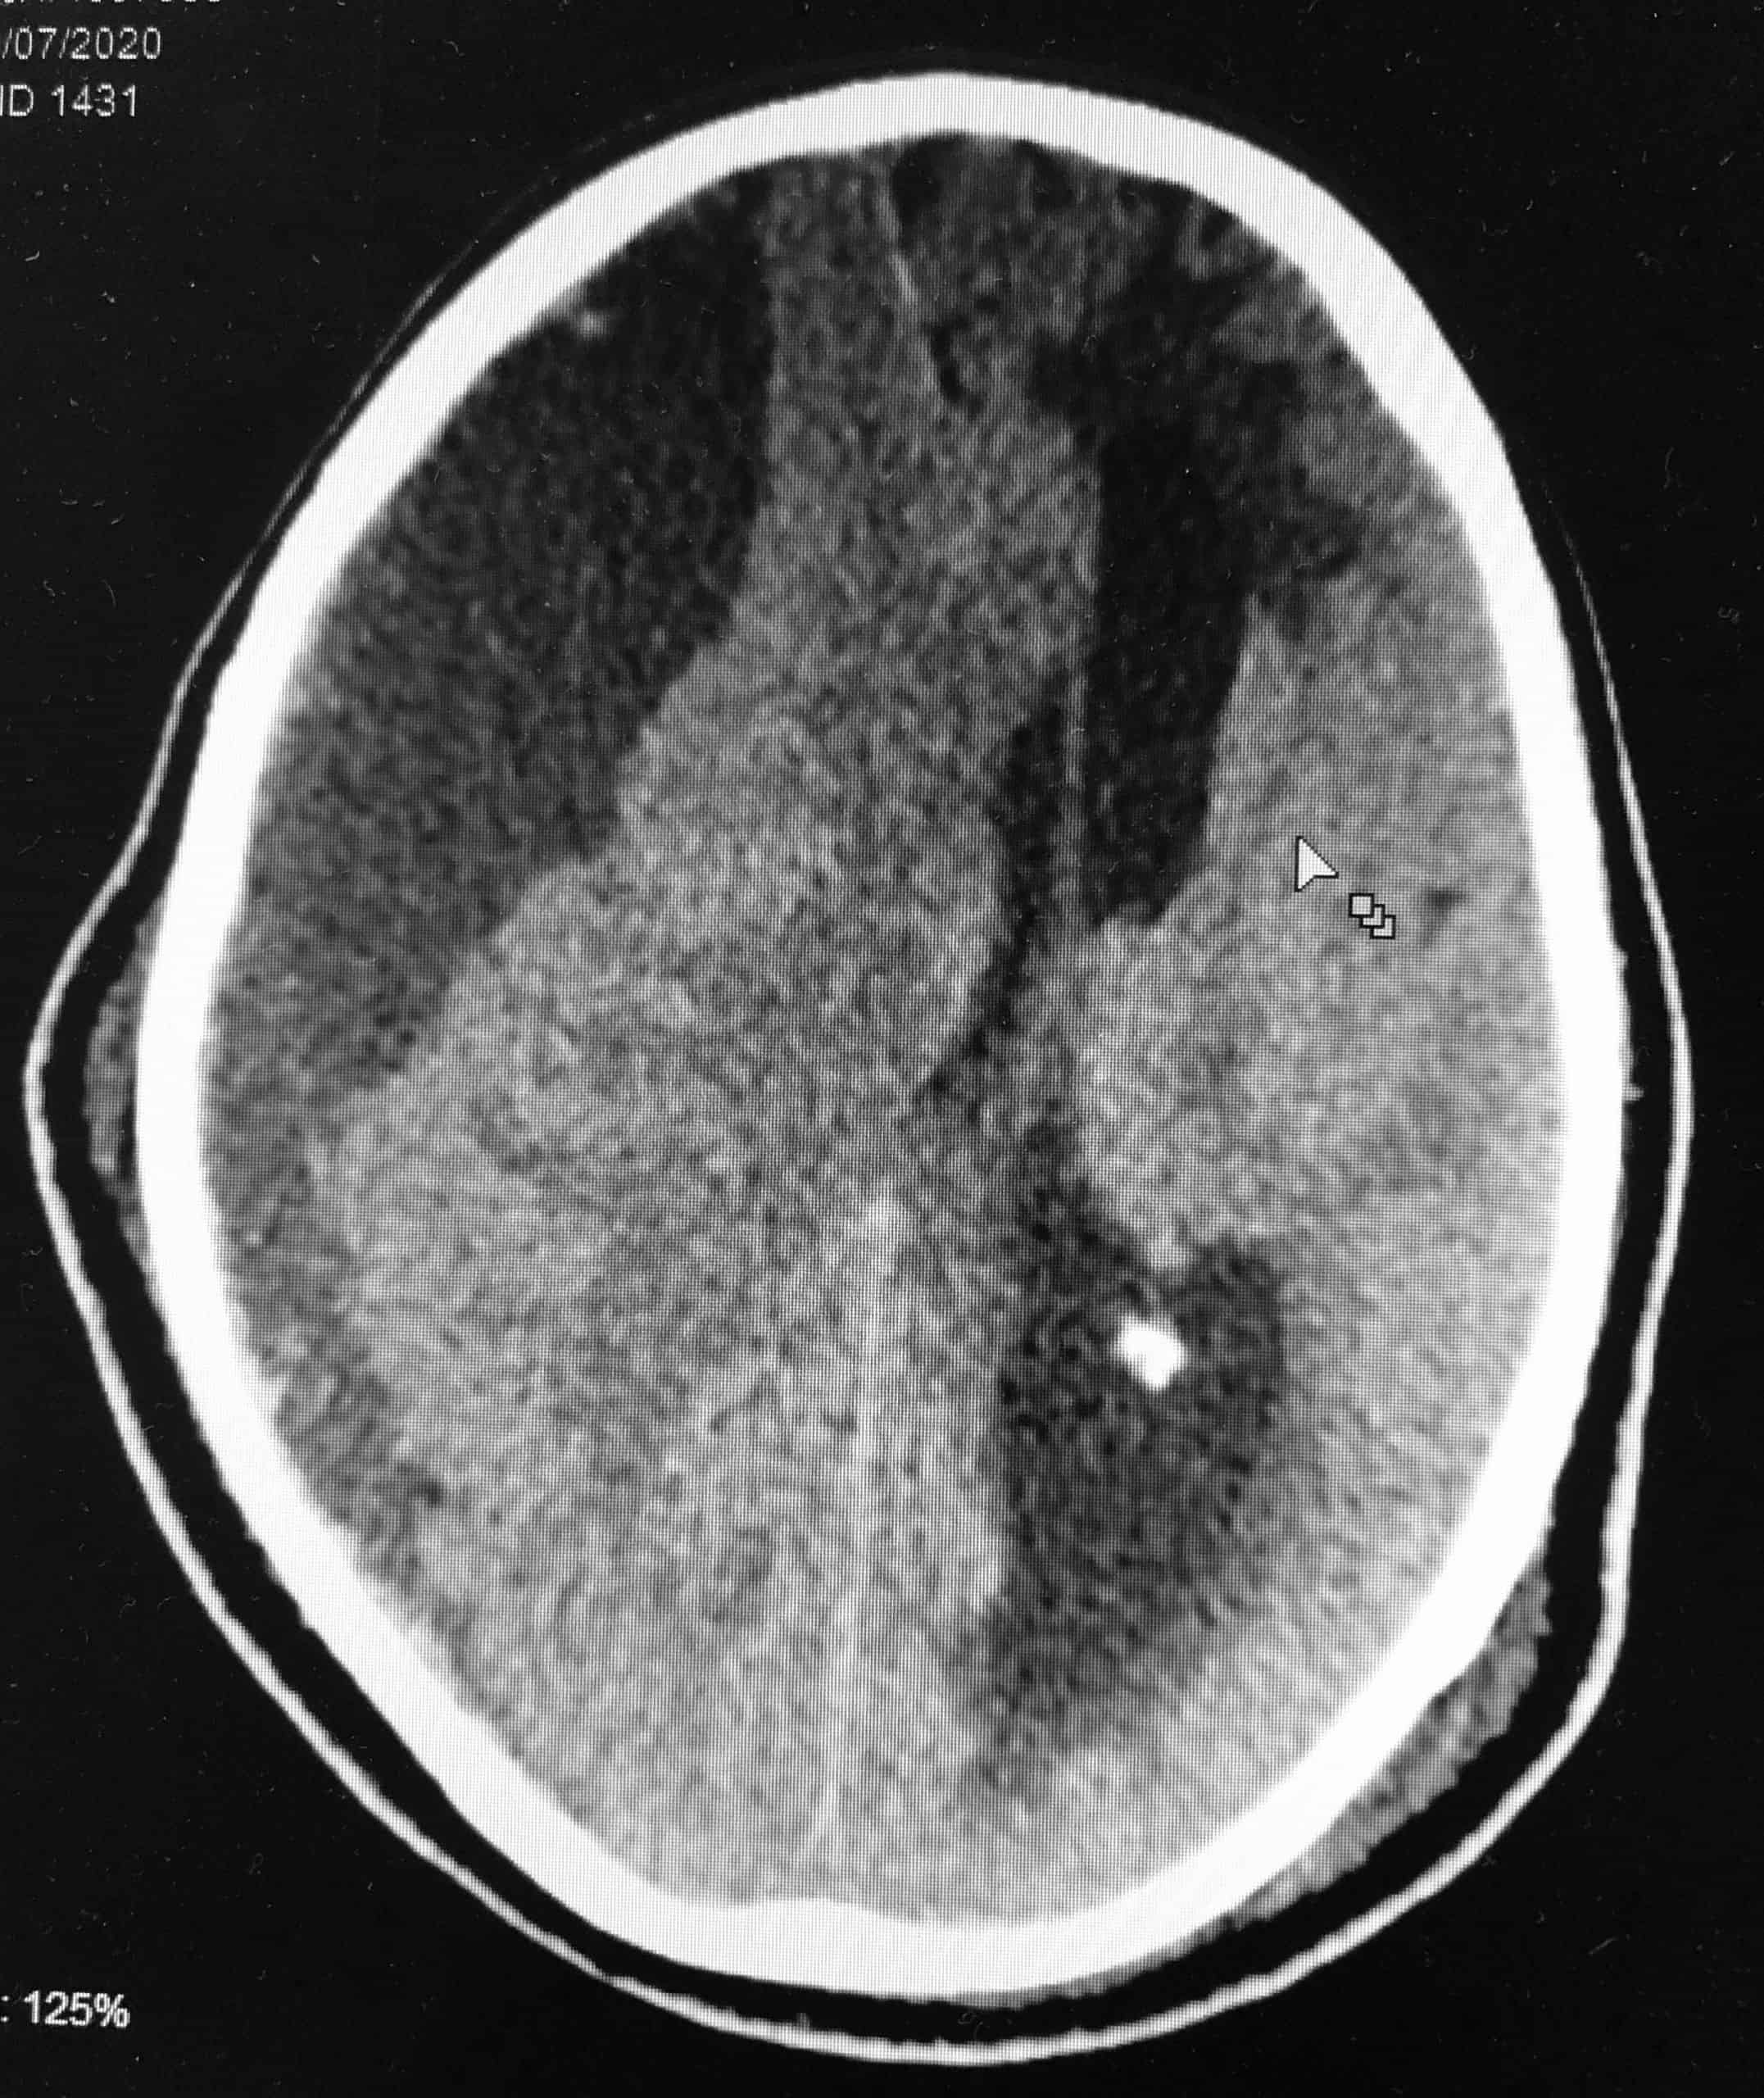

Um hematoma subdural crônico é constituído pela presença de sangramento crônico no espaço subdural, ou seja, abaixo da dura-máter (meninge rígida que envolve o cérebro). Ele se forma inicialmente em decorrência de algum traumatismo craniano, mesmo que mínimo, que cause hemorragia no espaço subdural. Esse sangramento estimula a formação de membranas e deposição de substâncias dentro do hematoma que provocam novos sangramentos, perpetuando o mesmo. Assim, ele pode atingir grandes dimensões como na imagem mostrada.